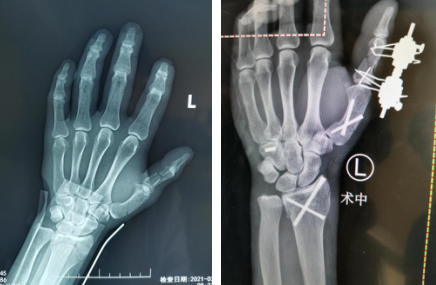

术前(左图)术中(右图)

术前

张师傅挂了手外科专家门诊号,恰好接诊的是二病区腕关节病专家齐伟亚主任。齐主任仔细询问了张师傅的受伤原因及就诊经历,为其进行了专科检查。检查结果显示,张师傅左手竟有大大小小五处骨折。左桡骨远端骨折,左腕钩状骨骨折,左第1掌骨骨折,左拇指骨折,左尺骨茎突骨折......张师傅一下子愣住了,没想到伤得这么严重,这可咋治呀?张师傅的家人恳求齐主任一定要给他治好,哪怕贵点也要用最好的药物,少让张师傅遭点罪。考虑张师傅及家人的诉求,结合其病情,齐主任安排他住院和手术治疗。

术前工作准备完毕,齐伟亚、刘桂谦手术团队为张师傅进行了进行了关节镜辅助下左桡骨远端骨折复位内固定+滑膜清扫,机器人导航下左腕钩状骨骨折复位内固定,左手第1掌骨骨折复位内固定,左拇指近节指骨骨折外固定架外固定,虽然手术时间稍长,但是手术很顺利,术后张师傅恢复良好,张师傅一家称赞齐主任的医技好,而且从患者的角度出发,不让患者多花一分钱。